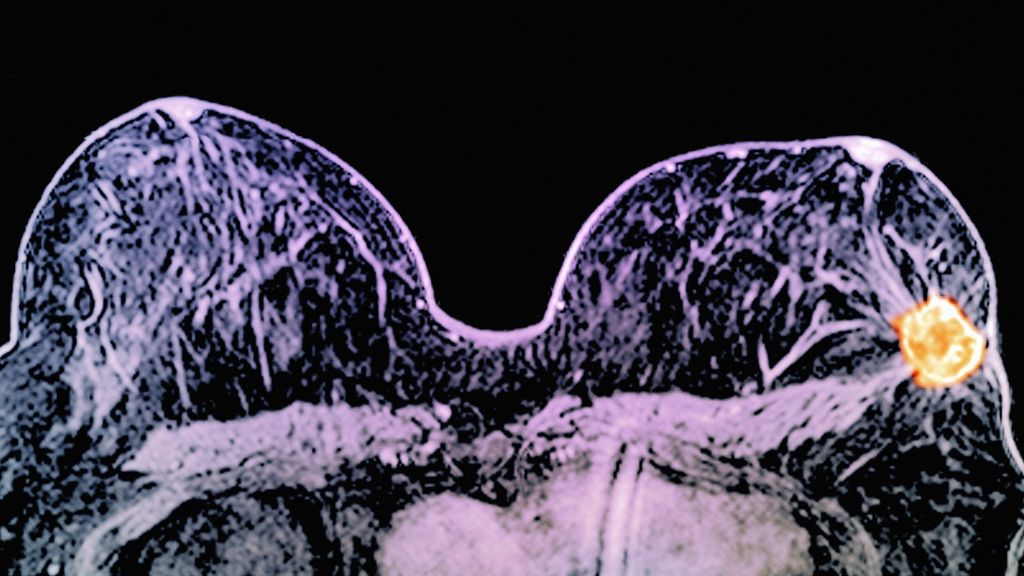

Ένας συνδυασμός δύο φαρμάκων, συρρικνώνει ή και ακόμη εξαφανίζει, έναν συγκεκριμένο τύπο όγκου καρκίνου του μαστού σε μόλις 11 ημέρες. Τα αποτελέσματα αναφέρθηκαν στην Ευρωπαϊκή Διάσκεψη για τον Καρκίνο του Μαστού στο Άμστερνταμ.

Ο συνδυασμός των φαρμάκων στοχεύει την πρωτεΐνη HER2, η οποία βρίσκεται σε περίπου έναν στους 10 καρκίνους του μαστού και είναι γνωστό ότι κάνει τους όγκους ιδιαίτερα επιθετικούς και ανθεκτικούς στη θεραπεία.

Η μελέτη διεξήχθη σε 257 γυναίκες που είχαν διαγνωστεί με θετικό HER2 καρκίνο του μαστού μεγέθους 1 έως 3 cm. Από τις συμμετέχουσες, οι 66 έλαβαν το συνδυασμό των δύο φαρμάκων και σε λιγότερο από δύο εβδομάδες, το 11% των γυναικών είδαν τους όγκους τους να εξαφανίζονται τελείως. Μόνο το 17% είχε όγκους κάτω των 5 mm σε μέγεθος.

Τα φάρμακα είναι η λαπατινίμπη (Tyverb) και η τραστουζουμάμπη (Herceptin).

Και τα δύο αυτά φάρμακα είναι γνωστό ότι στοχεύουν τον HER2. Το Herceptin στοχεύει την επιφάνεια των καρκινικών κυττάρων, ενώ η λαπατινίμπη είναι ικανή να διεισδύσει στα κύτταρα και να επιτίθεται μέσα σε αυτά.